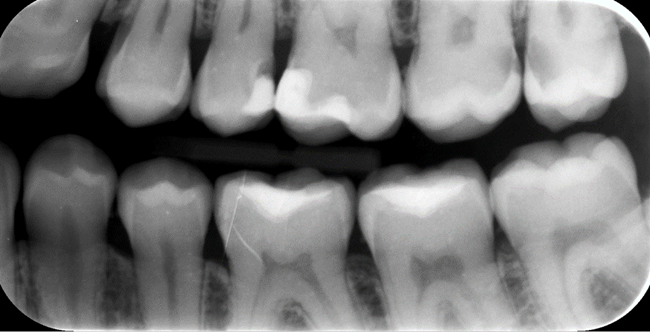

W procesie diagnostyki próchnicy wykorzystuje się metodę wizualno-dotykową i metody radiologiczne – a dokładniej zdjęcia skrzydłowo-zgryzowe, które wspólnie stanowią złoty standard w wykrywaniu i rozpoznawaniu zmian próchnicowych (ryc. 1).

Ryc. 1. Zdjęcie skrzydłowo-zgryzowe obrazujące m.in. próchnicę zębów na powierzchniach stycznych.